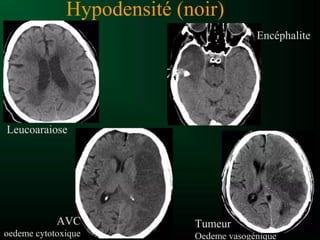

• en TDM chaque structure observée est décrite

selon sa densité

• Hyperdense : apparait plus dense que son

environnement

• Hypodense : densité plus faible

• Isodense : densité similaire

• oedème périlésionnel : hypodensite entourant

un processus pathologique